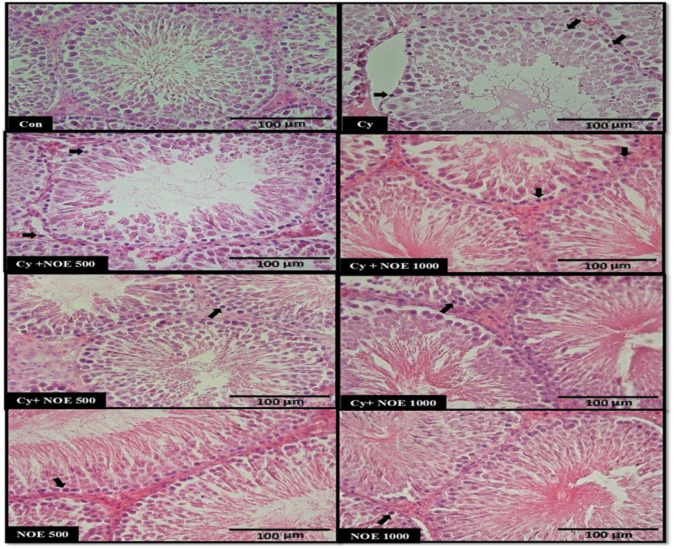

Materials and methods: Forty-eight adult male Wistar rats were randomly allocated into eight groups (n=6): control, Cy [received a single dose of 75 mg/kg, intraperitoneal (i.p)], NOE+Cy (Prevention): received NOE 500 and 1000 mg/kg/day, orally for 21 consecutive days and on the last day received Cy, Cy+NOE (Treatment): received NOE 500 and 1000 mg/kg/day, orally for 7 days after Cy administration for 21 consecutive days, and NOE (500 and 1000 mg/kg/day). After experiments, the testicular weight and volume, testosterone level, and sperm parameters as well as histologic and histomorphometric changes of testis were examined.

Results: Base on the results, Cy caused significant decreases in testicular weight and volume, decreased testosterone level and reduced sperm count, and motility whereas increased sperm abnormality (p<0.05). Cy significantly reduced seminiferous tubules diameter, and height of the seminiferous epithelium (p<0.05). Furthermore, disorganization of seminiferous tubules diameter was increased in Cy group (p<0.05). Interestingly, pre and post-treatment with NOE could effectively improve testicular weight and volume, and testosterone level as well as sperm parameters. Furthermore, NOE administration ameliorated seminiferous tubules diameter diameter, seminiferous epithelium height (p<0.05).

Conclusion: It is concluded that NOE may provide a potential protective effect for Cy-induced testicular damage.